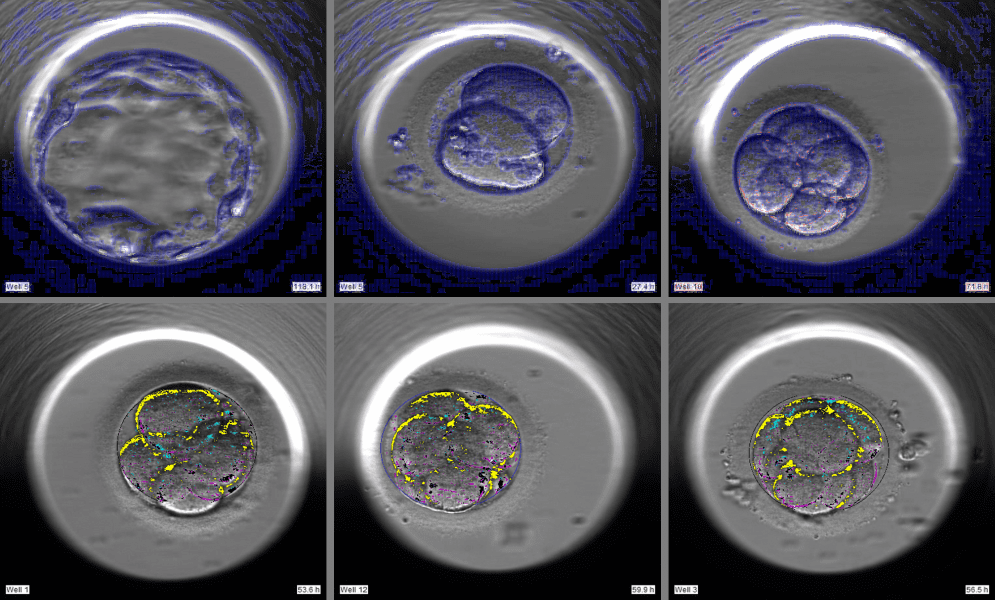

[caption id="attachment_53512" align="alignnone" width="1966"]

AIVF's deep learning and computer vision algorithms applied to time-lapse videos and stills of embryo development with proprietary markers and identifiers. Photo: Courtesy.[/caption]

With these time-lapse videos, the company is developing AI algorithms using a combination of deep learning and computer vision methodologies. Using a combination of AI methodologies, like convolutional neural networks to proprietary image processing systems designed for the unique characteristics of these relatively new time-lapse images, AIVF is at the forefront of the application of technology to revolutionize IVF process.